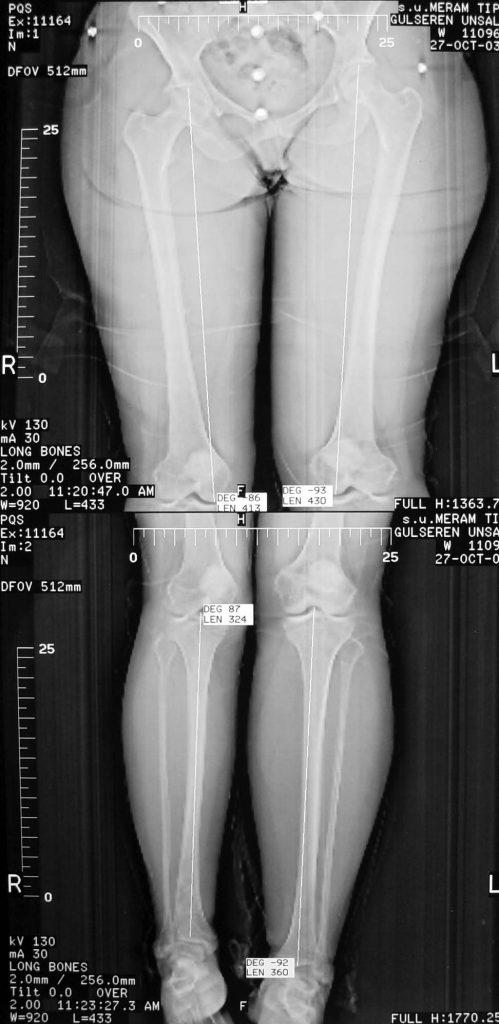

Vaka 2